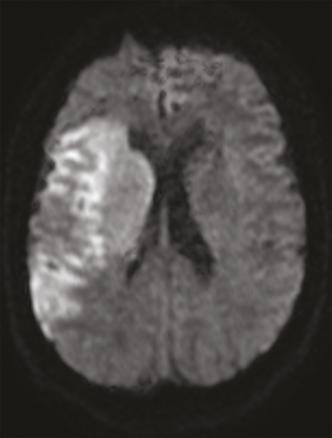

Cet homme de 41 ans, sans antécédent notable, était admis aux urgences pour une hémiplégie gauche d’apparition brutale (H3). Une angio-IRM cérébrale montrait un infarctus frontal et dans le territoire de l’artère sylvienne superficielle et profonde droit (fig. 1 ). Étant donné son jeune âge, un angioscanner des troncs supra-aortiques était réalisé, montrant une image d’éperon caractéristique de diaphragme bulbaire carotidien (fig. 2 ). Le patient était hospitalisé, mis sous traitement médical à base d’anticoagulant à dose préventive et d’antiagrégant plaquettaire en attendant la réalisation d’une artériographie avec mise en place d’un stent.

Le diaphragme carotidien est une pathologie rare à l’origine d’accidents vasculaires cérébraux ischémiques du sujet jeune. Il s’agit d’une prolifération intimale située le plus souvent à la face postérieure du bulbe carotidien réalisant un voile endoluminal, entraînant la formation d’emboles et responsable d’infarctus cérébraux par embolie des grosses artères ; son diagnostic est essentiel parce qu’il expose à un risque élevé de récidive dans le même territoire vasculaire. L’angioscanner des troncs supra-aortiques avec reconstruction en coupe sagittale montre un éperon endoluminal caractéristique. Le siège de prédilection est le bulbe carotidien ; d’autres localisations ont été décrites, notamment la carotide commune1 et l’artère carotide interne. L’angiographie numérisée à but thérapeutique montre le diaphragme, la stase du flux sanguin dans le récessus créé et, image caractéristique, la stagnation du produit de contraste. Le traitement consiste en un stenting endovasculaire et une endartériectomie associée à une antiagrégation plaquettaire à vie ;2 une surveillance rapprochée est préconisée, nécessitant un examen neurologique et une échographie doppler 3 mois après, puis annuellement pendant 5 ans. La double antiagrégation plaquettaire est préconisée pendant 3 mois, donnant relais à une monothérapie à base d’aspirine à vie.